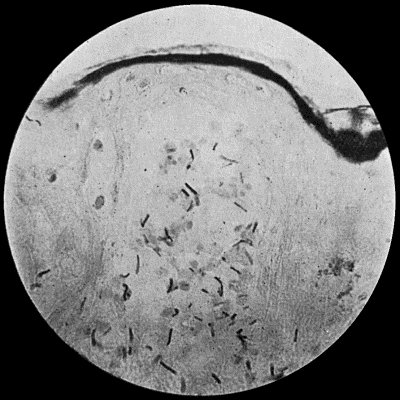

| 10. | Charts of Acute Sapræmia | 61 |

| 11. | Chart of Hectic Fever | 62 |

| 12. | Chart of Septicæmia followed by Pyæmia | 63 |

| 13. | Chart of Pyæmia following on Acute Osteomyelitis | 65 |